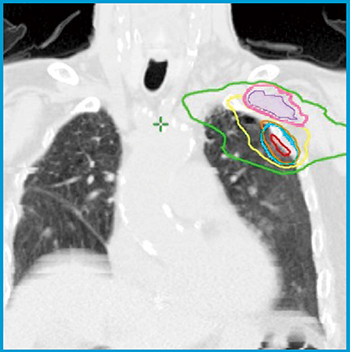

図3 左上葉肺腺癌1

病巣は腕神経叢に近接して存在する。PTVと計画リスク臓器体積(PRV)の最短距離は3mmであった。腕神経叢の最大線量は33Gy,それに3mmを付与したPRVの最大線量は41Gyであることを確認し,SBRTを行った。 *治療計画前に上肢挙上と下げた場合の2種類の体位でCTを撮影し,PTVとPRVがより離れている姿勢で治療計画を行う。

腕神経叢(○),PRV(=腕神経叢+3mm)(○),PTV(○),等線量曲線は外側より16.7Gy(○),33.3Gy(○),50Gy(=処方線量)(○),66.7Gy(○)